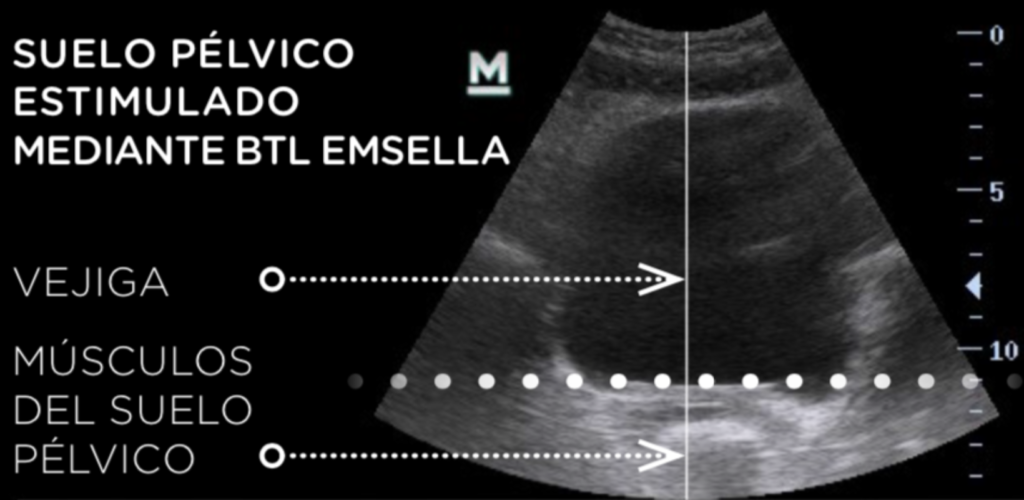

Repara y tensa el suelo pélvico ayudando a HOMBRES y MUJERES a recuperar el control de su vejiga.

Usamos la tecnología de vanguardia. Es una silla diseñada específicamente para fortalecer los músculos del piso pélvico, rehabilitarlos y reeducarlos, generando contracciones supramaximas que en tan solo media hora emiten la energía equivalente a realizar 11,200 ejercicios de KEGEL.

Los ejercicios de Kegel son una fórmula APROBADA y RECOMENDADA, una vez por ginecólogos, Urólogos, médicos rehabilitadores y geriatras. Lo que hacemos con Emsella es llevarlos a su MÁXIMA EFICACIA devolviendo la fortaleza y elasticidad al piso pélvico y también a los músculos de la vagina de manera integral.